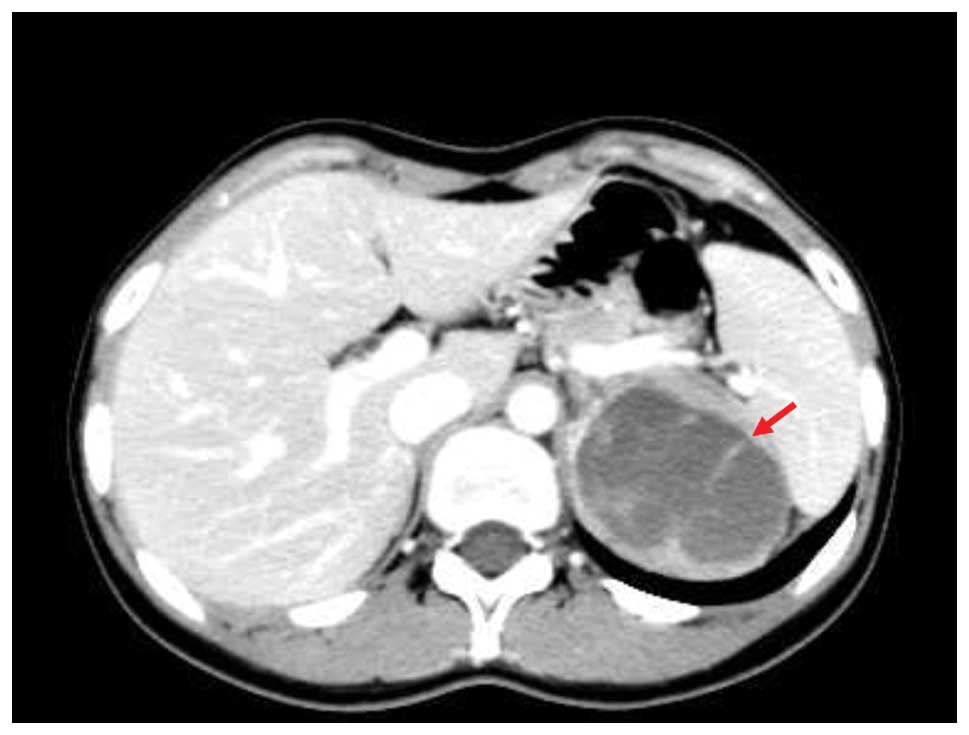

A 22-year-old female was referred to the First Affiliated Hospital of Zhejiang University School of Medicine, Zheijang, China, due to the presence of a retroperitoneal 5.9×5.3-cm mass in the left adrenal region that was detected by B ultrasound (BUS) imaging during a routine annual examination (Fig. 1). The patient did not complain of fatigue, fever or pain, and the patient’s body weight and blood pressure were within the corresponding normal ranges. The complete blood count, chemistry panel, urine analysis and liver function test results were also normal. An endocrinological evaluation of the adrenal gland, including an analysis of the plasma rennin activity and aldosterone, steroid and catecholamine levels, excluded a functional adenoma. Abdominal computed tomography (CT) revealed that the retroperitoneal mass was solid, encapsulated and ∼6 cm in diameter, with low attenuation and containing solid and cystic components. The mass was located in the adrenal region; positioned close to the pancreatic tail, behind the stomach and between the spleen and the aorta (Fig. 2). Since the diagnosis of an adrenal tumor was not excludable based on the results of the BUS and CT examinations, the patient was scheduled for laparoscopic adrenalectomy. During the surgery, the pancreas and left adrenal gland were in contact and clearly separated from the tumor. The main blood supplies originated from branches of the splenic artery. The tumor was completely removed from the retroperitoneum during this laparoscopy.

Figure 2

Computed tomography scan showing an adrenal mass suspected to be a possible adrenal tumor.